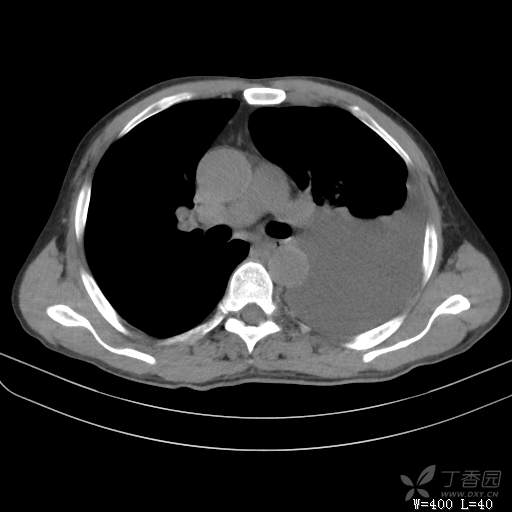

简要病史:胸闷、憋气伴低热1月

辅助检查:白细胞数目4.41 × 10^9/L,中性粒细胞百分比82.1%,*血红蛋白111g/L,*血小板数目91 × 10^9/L,凝血四项:凝血酶原时间12.5秒,国际标准化比值1.07,活化部分凝血酶原时间36.1秒,纤维蛋白原浓度6.52g/L,肾功能示:肌酐47.4umol/L,尿酸150umol/L,电解质示:钠133.5mmol/L,D-二聚体0.88mg/L,血沉67.71MM/H,C-反应蛋白114.6mg/L,肝功能:*总蛋白49.6g/L,*白蛋白27.4g/L,查胸水常规及胸水生化提示渗出液,胸水ADA154U/L,查胸水病理未见肿瘤细胞。超声:腹膜后有3~4枚肿大淋巴结,直径1~1.5厘米,余浅表淋巴结不大。

临床诊断:左侧胸腔积液

治疗经过:胸水引流。胸水白蛋白23.8克/升,乳酸脱氢酶275单位/升,胸苷激酶182单位/升,胸水外观黄色混浊,总细胞4320个/微升,白细胞4320个/微升,单核细胞80%,多核细胞20%。考虑结核性胸膜炎,结果查肿瘤标志物、胸水细胞学阴性,胸水TB—DNA阴性,结核菌素试验+,结核抗体阴性,TB-SPOT阴性,胸膜活检阴性。怎么办?